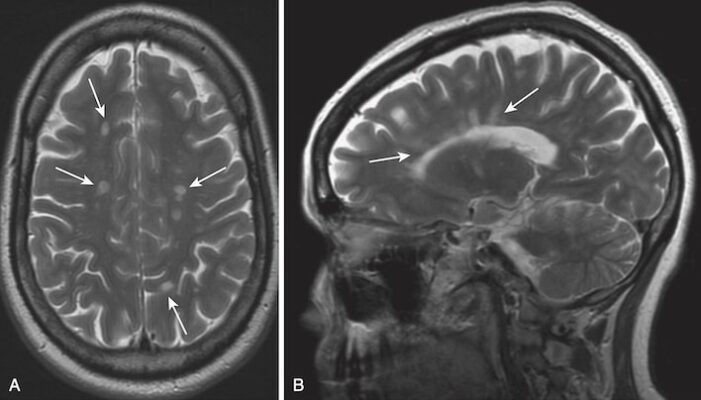

Xơ cứng rải rác

- Xơ cứng rải rác (Multiple sclerosis, MS) được xem là bệnh có nguồn gốc tự miễn dịch và là bệnh mất myelin thường gặp nhất. Bất kỳ chức năng thần kinh nào cũng có thể bị ảnh hưởng bởi bệnh này, với một số bệnh nhân chủ yếu có những thay đổi về nhận thức, trong khi những bệnh nhân khác bị thất điều, yếu liệt hoặc có triệu chứng về thị giác.

- Điển hình đặc trưng bởi tiến triển tái phát và thuyên giảm, chẩn đoán MS cần xác định các tiêu chuẩn lâm sàng cụ thể, nhưng hình ảnh học bằng MRI cùng với các xét nghiệm hỗ trợ giờ đây cho phép chẩn đoán sau một đợt duy nhất.

- Bệnh đặc trưng ảnh hưởng đến các bó (chất trắng) có myelin với các tổn thương được gọi là mảng (plaques). Các tổn thương của bệnh Xơ cứng rải rác có xu hướng ở vùng quanh não thất, thể chai và các dây thần kinh thị giác.

- MRI là nghiên cứu được chọn lựa trong chẩn đoán hình ảnh bệnh Xơ cứng rải rác nhạy hơn CT trong việc chứng minh các mảng ở não và cả tủy sống.

- Tổn thương tạo ra các ổ hình cầu, rời rạc, có cường độ tín hiệu cao (màu trắng) trên T2W.

- Trên hình ảnh T1W không cản quang, các ổ này giảm tín hiệu hoặc đẳng tín hiệu, nhưng trong MS cấp tính, các tổn thương tăng cường tín hiệu với gadolinium trên hình ảnh T1W.

- Các tổn thương có xu hướng định hướng với các trục dài của chúng vuông góc với thành não thất (Hình 31).